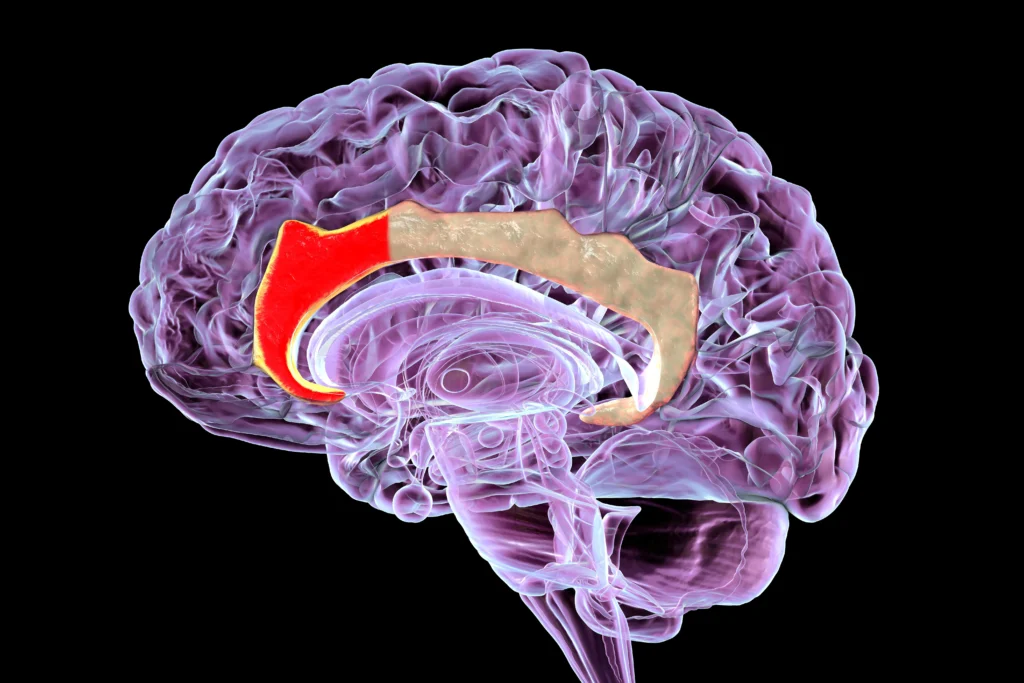

3. Anterior Cingulate Cortex (ACC)

This is the front part of the cingulate gyrus and plays a role in speech, emotional response, and the perception of pain. Its activity increases when a person faces anticipated fears or threats. According to studies, ACC activity is elevated in individuals with anxiety.

As a result of this increase, the brains of anxiety patients suffer from intense focus on risks and excessive monitoring and rumination on negative thoughts, which raises tension levels and deprives the person of relaxation and mental peace.

4. Prefrontal Cortex (PFC)

Unlike the previous regions, the prefrontal cortex shows less activity in individuals with anxiety disorders. It is responsible for conscious thought and emotional control, and it exerts inhibitory functions over the hyperactivity of parts of the limbic system, such as the amygdala.

Therefore, the ability of anxiety patients to control their worries and maintain composure during stressful situations is diminished due to the dominance of fear centers like the amygdala and insula, which corresponds to reduced activity in the prefrontal cortex.